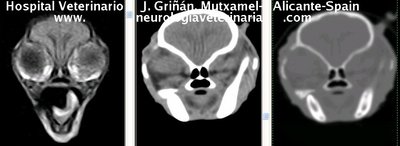

Se muestran cortes transversales de Resonancia Magnética (imagen a la izqda del lector), TC contrastado para tejidos blandos (imagen del centro) y TC contrastado para tejidos duros (imagen de la derecha del lector).

Nótese como la Resonancia supera al TC en el contraste de tejidos blandos (encéfalo y médula espinal) y en el de líquidos (ojo y líquido cefalorraquídeo), mientras que el TC supera a la resonancia en el contraste de tejidos duros (hueso) y aire (senos, cavidad nasal y bullas)

Cortes a nivel del diencéfalo (hipófisis) y lóbulos piriformes. Nótense sendos ventrículos laterales y tercer ventrículo